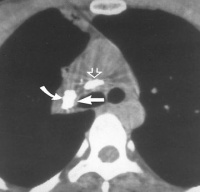

影像学表现:肺门有钙化的淋巴结阴影。钙化的位置和数目在不同时间照片上可有变化。结石阻塞支气管后可发生阻塞性肺炎或肺不张。相应的肺组织内有斑片状阴影,体积缩小。结石阻塞的支气管远端发生支气管粘液栓塞后形成柱状、“V”型或“Y”型致密阴影。